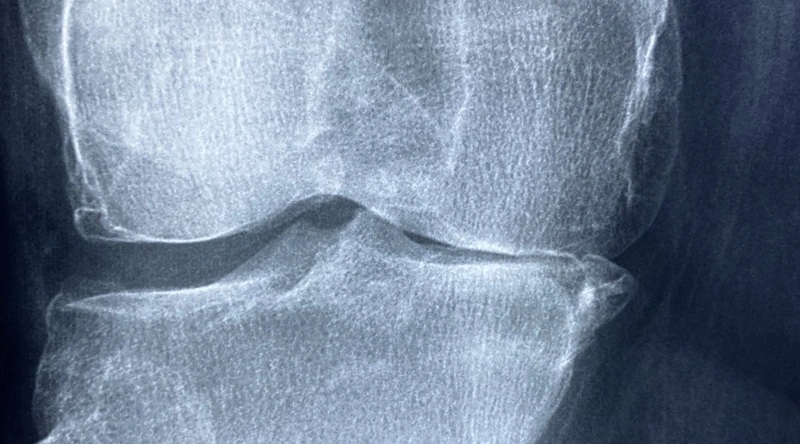

관절염은 여러 종류가 있으며, 그 원인은 다양합니다. 가장 흔한 형태인 퇴행성 관절염은 나이와 함께 관절의 연골이 닳아 없어지는 것으로, 통증, 부기, 운동 범위 감소 등의 증상을 동반합니다. 또한, 류마티스 관절염과 같은 자가면역 질환도 관절 건강에 심각한 영향을 미칠 수 있습니다. 이러한 질환들은 일상생활에 큰 영향을 미치며, 조기에 대응하지 않으면 증상이 악화될 수 있습니다.